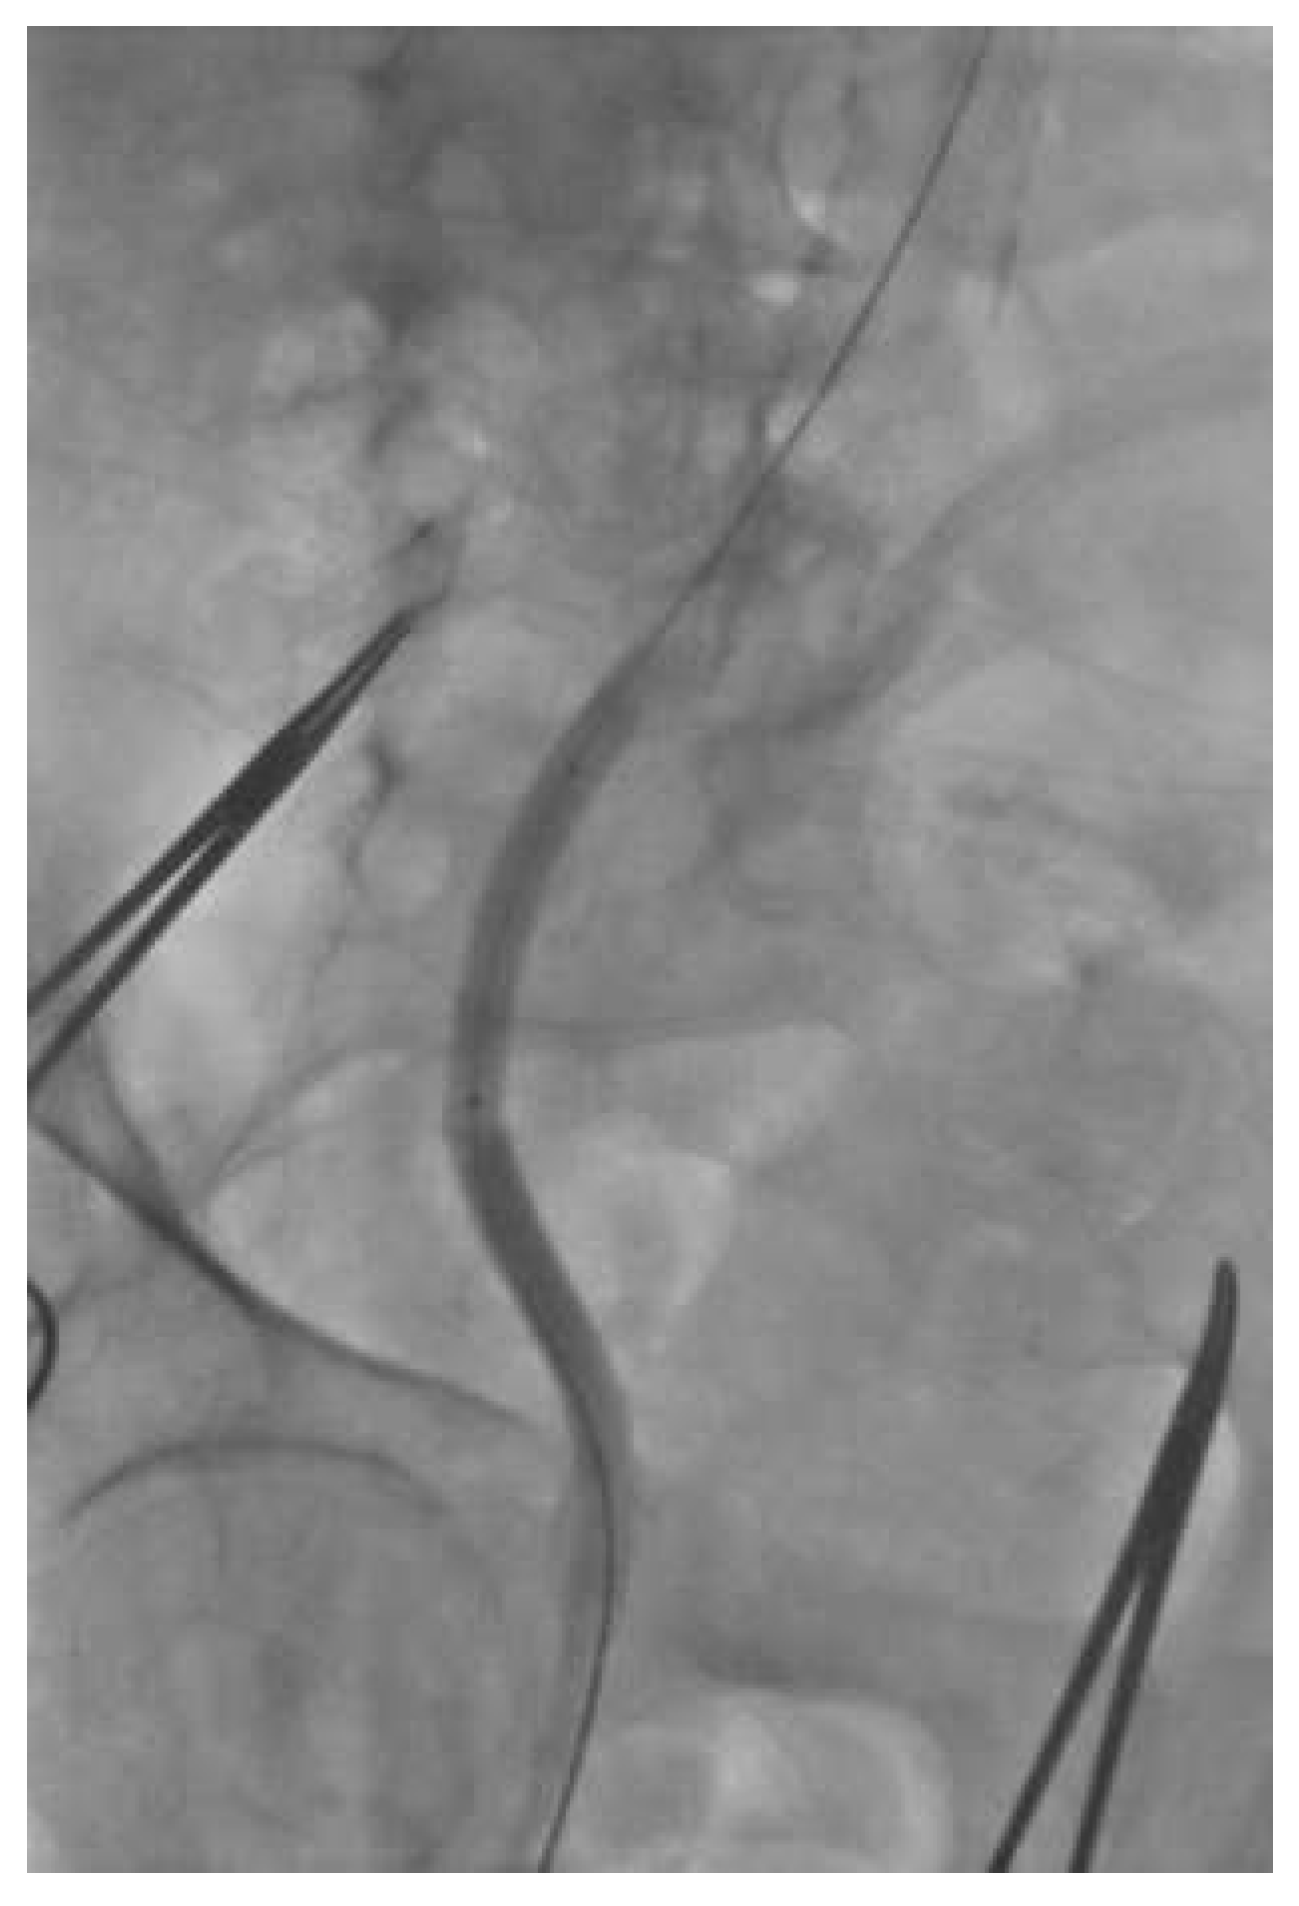

Under local anaesthesia and conscious sedation, we punctured the common femoral artery and performed the pre-closure technique using the Prostar® XL10 (Abbott Vascular, Reedwood City, CA). Over a Super Stiff ST-1 wire (Boston Scientific, Maple Grove, MN, USA) we inserted a folded 19-French SoloPath® sheath without any difficulties. As recommended by the instructions for use, once the sheath was full inserted we inflated the sheath balloon at 20 atmospheres for one minute. As we commonly did with other large-bore sheaths, the stiff wire was retrieved simultaneously with the dilator. At this time we noticed a kink in the sheath at the level of the iliac tortuosity (Figure 3), this kink was overcome with some difficulty by advancing a 0.035” wire. Subsequently, the kinked portion of the sheath was dilated with a peripheral balloon catheter (Admiral Xtreme 7 × 40 mm; Medtronic, MN, USA) (Figure 4). However, since we were not satisfied with that aspect of the sheath and we feared difficulties in advancement or retrieval of equipment during the procedure, we preferred to exchange the SoloPath® sheath for an 18-F Cook sheath (Cook Medical, Bloomington, IN, USA), which completely straightened the vessel (Figure 5). The procedure was then completed by pre-dilatation and successful implantation of a 29 Medtronic CoreValve®. The final ilio-femoral angiography from the contralateral femoral access showed no vascular complication or bleeding.

Figure 3. 19-F SoloPath® sheath (Onset Medical) with a kink.